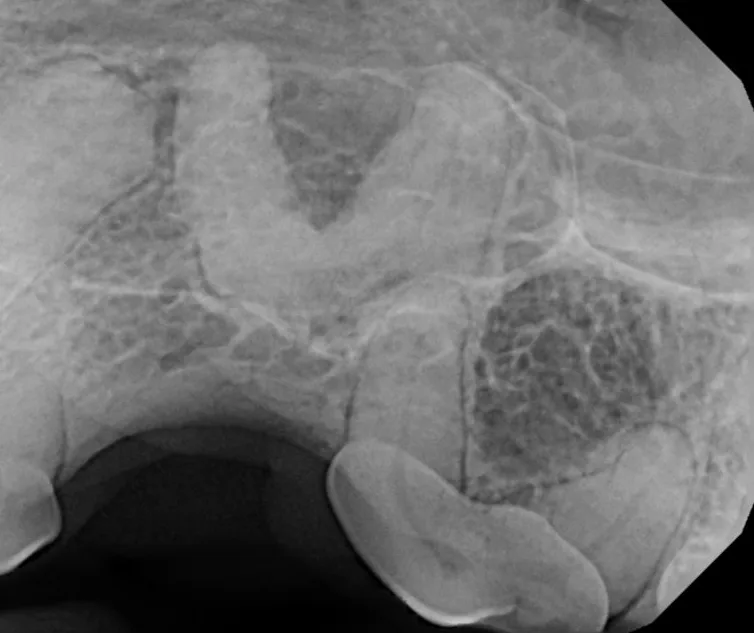

The Center now provides advanced imaging via cone beam CT. Cone beam CT is excellent for visualization of bony structures of the skull, nasal cavity, teeth, and ears. Cone beam CT is especially helpful for diagnosing dental disease and evaluation of jaw fractures. It can also be useful for evaluating the sinuses and tympanic bulla. Cone beam CT can be used in conjunction with nasal biopsy and culture to evaluate nasal discharge whether chronic or acute.

Tooth resorption is a disease process where the body begins to break down the adult tooth. It is widely known to occur in cats but can also occur in dogs. In cats these lesions are thought to be inflammatory, while in dogs they can be more of a replacement resorption process. These lesions can be very painful and should be treated, generally with extraction depending on the type of resorption that is occurring. The disease can be progressive and affect many teeth over several years. It is important to have regular checkups and yearly dental cleanings to monitor for these lesions.